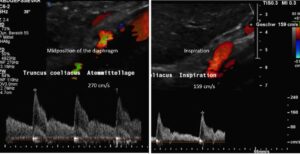

The chronic regional pain syndrome component was fuelled by activation of the sympathetic nervous system, resulting from compression of the largest sympathetic nerve plexus: the celiac plexus. In this patient, the coeliac plexus was severely compressed by a tightly straddling median arcuate ligament at the origin of the coeliac trunk. This is another consequence of increased lumbar lordosis, which pulls the arch formed by the two diaphragmatic crus legs tight.

In arcuate ligament syndrome, the coeliac plexus is compressed between the lower margin of the aortic hiatus and the coeliac artery. This results in persistent mechanical activation of this large sympathetic nervous network.

It was understood that sympathetic activation produced arterial hyperperfusion of the affected limb, as well as multiple obstructions to venous drainage, both of which contributed to swelling, pain, discolouration, and hypersensitivity in the left leg.